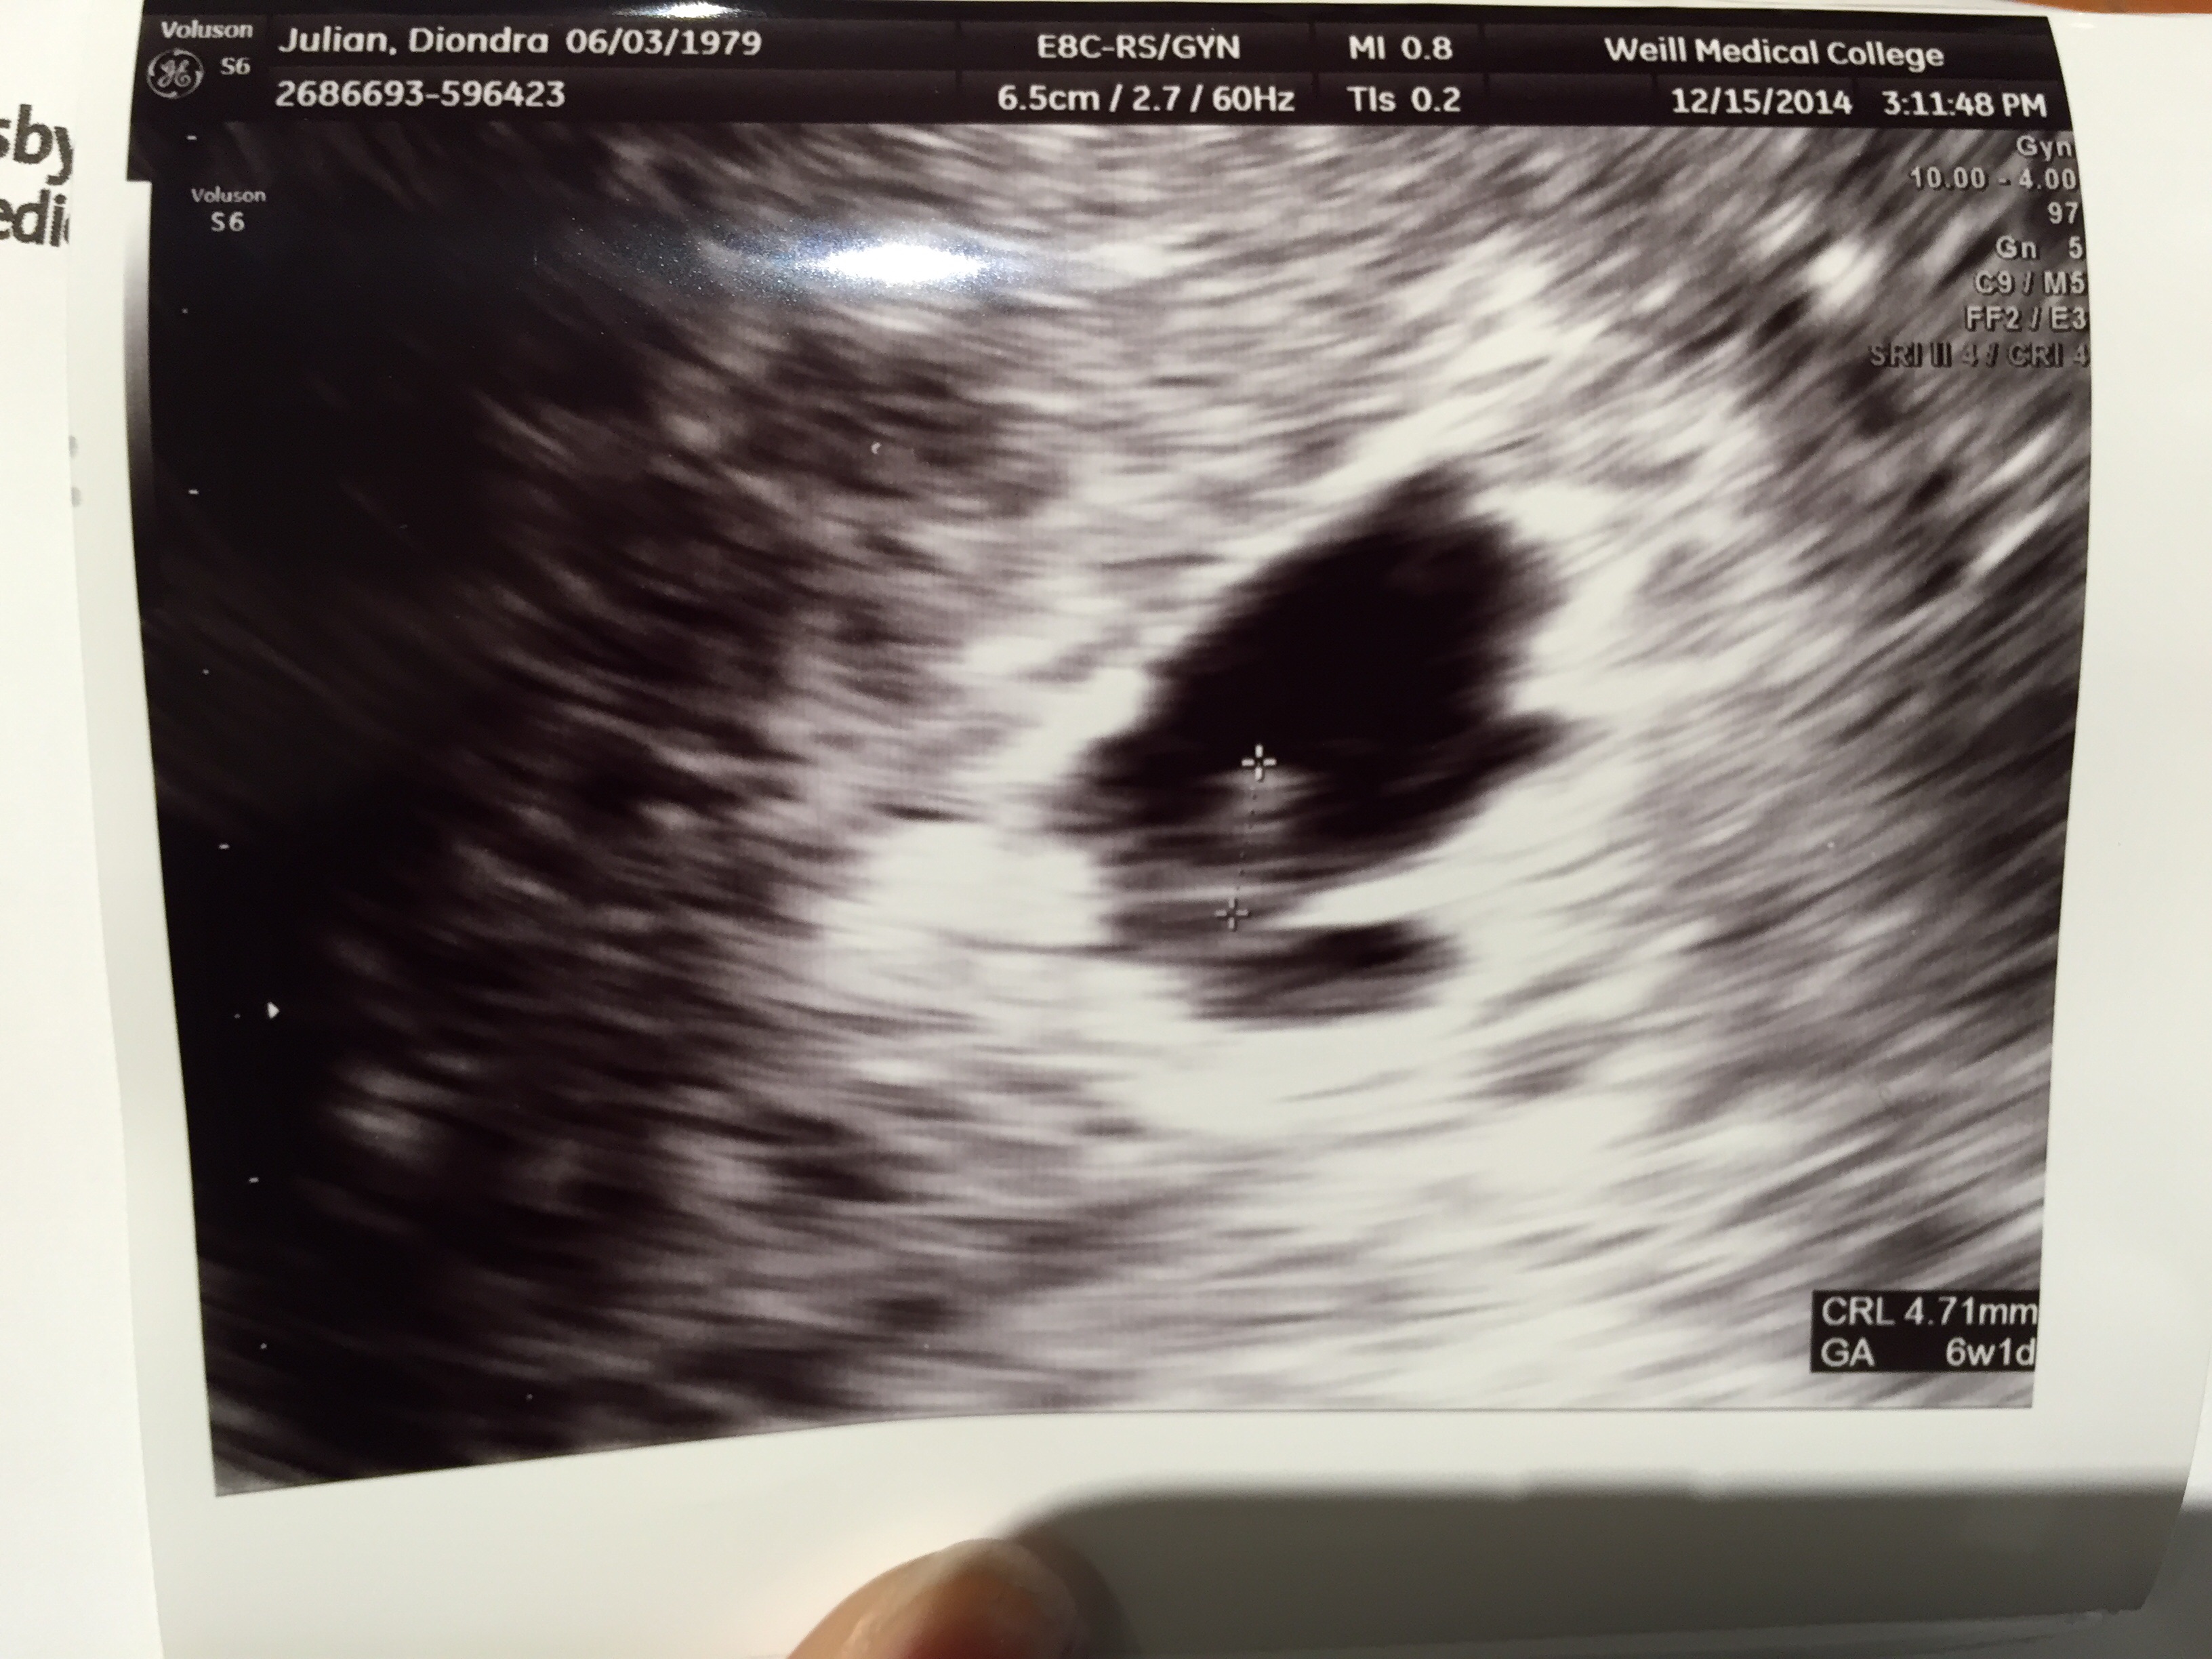

• Had my ultrasound today. Was measuring 6w6d (was 7 weeks by LMP but 6&6 makes sense). Heart rate was 118 BPM which is scaring me because it seems a little low.